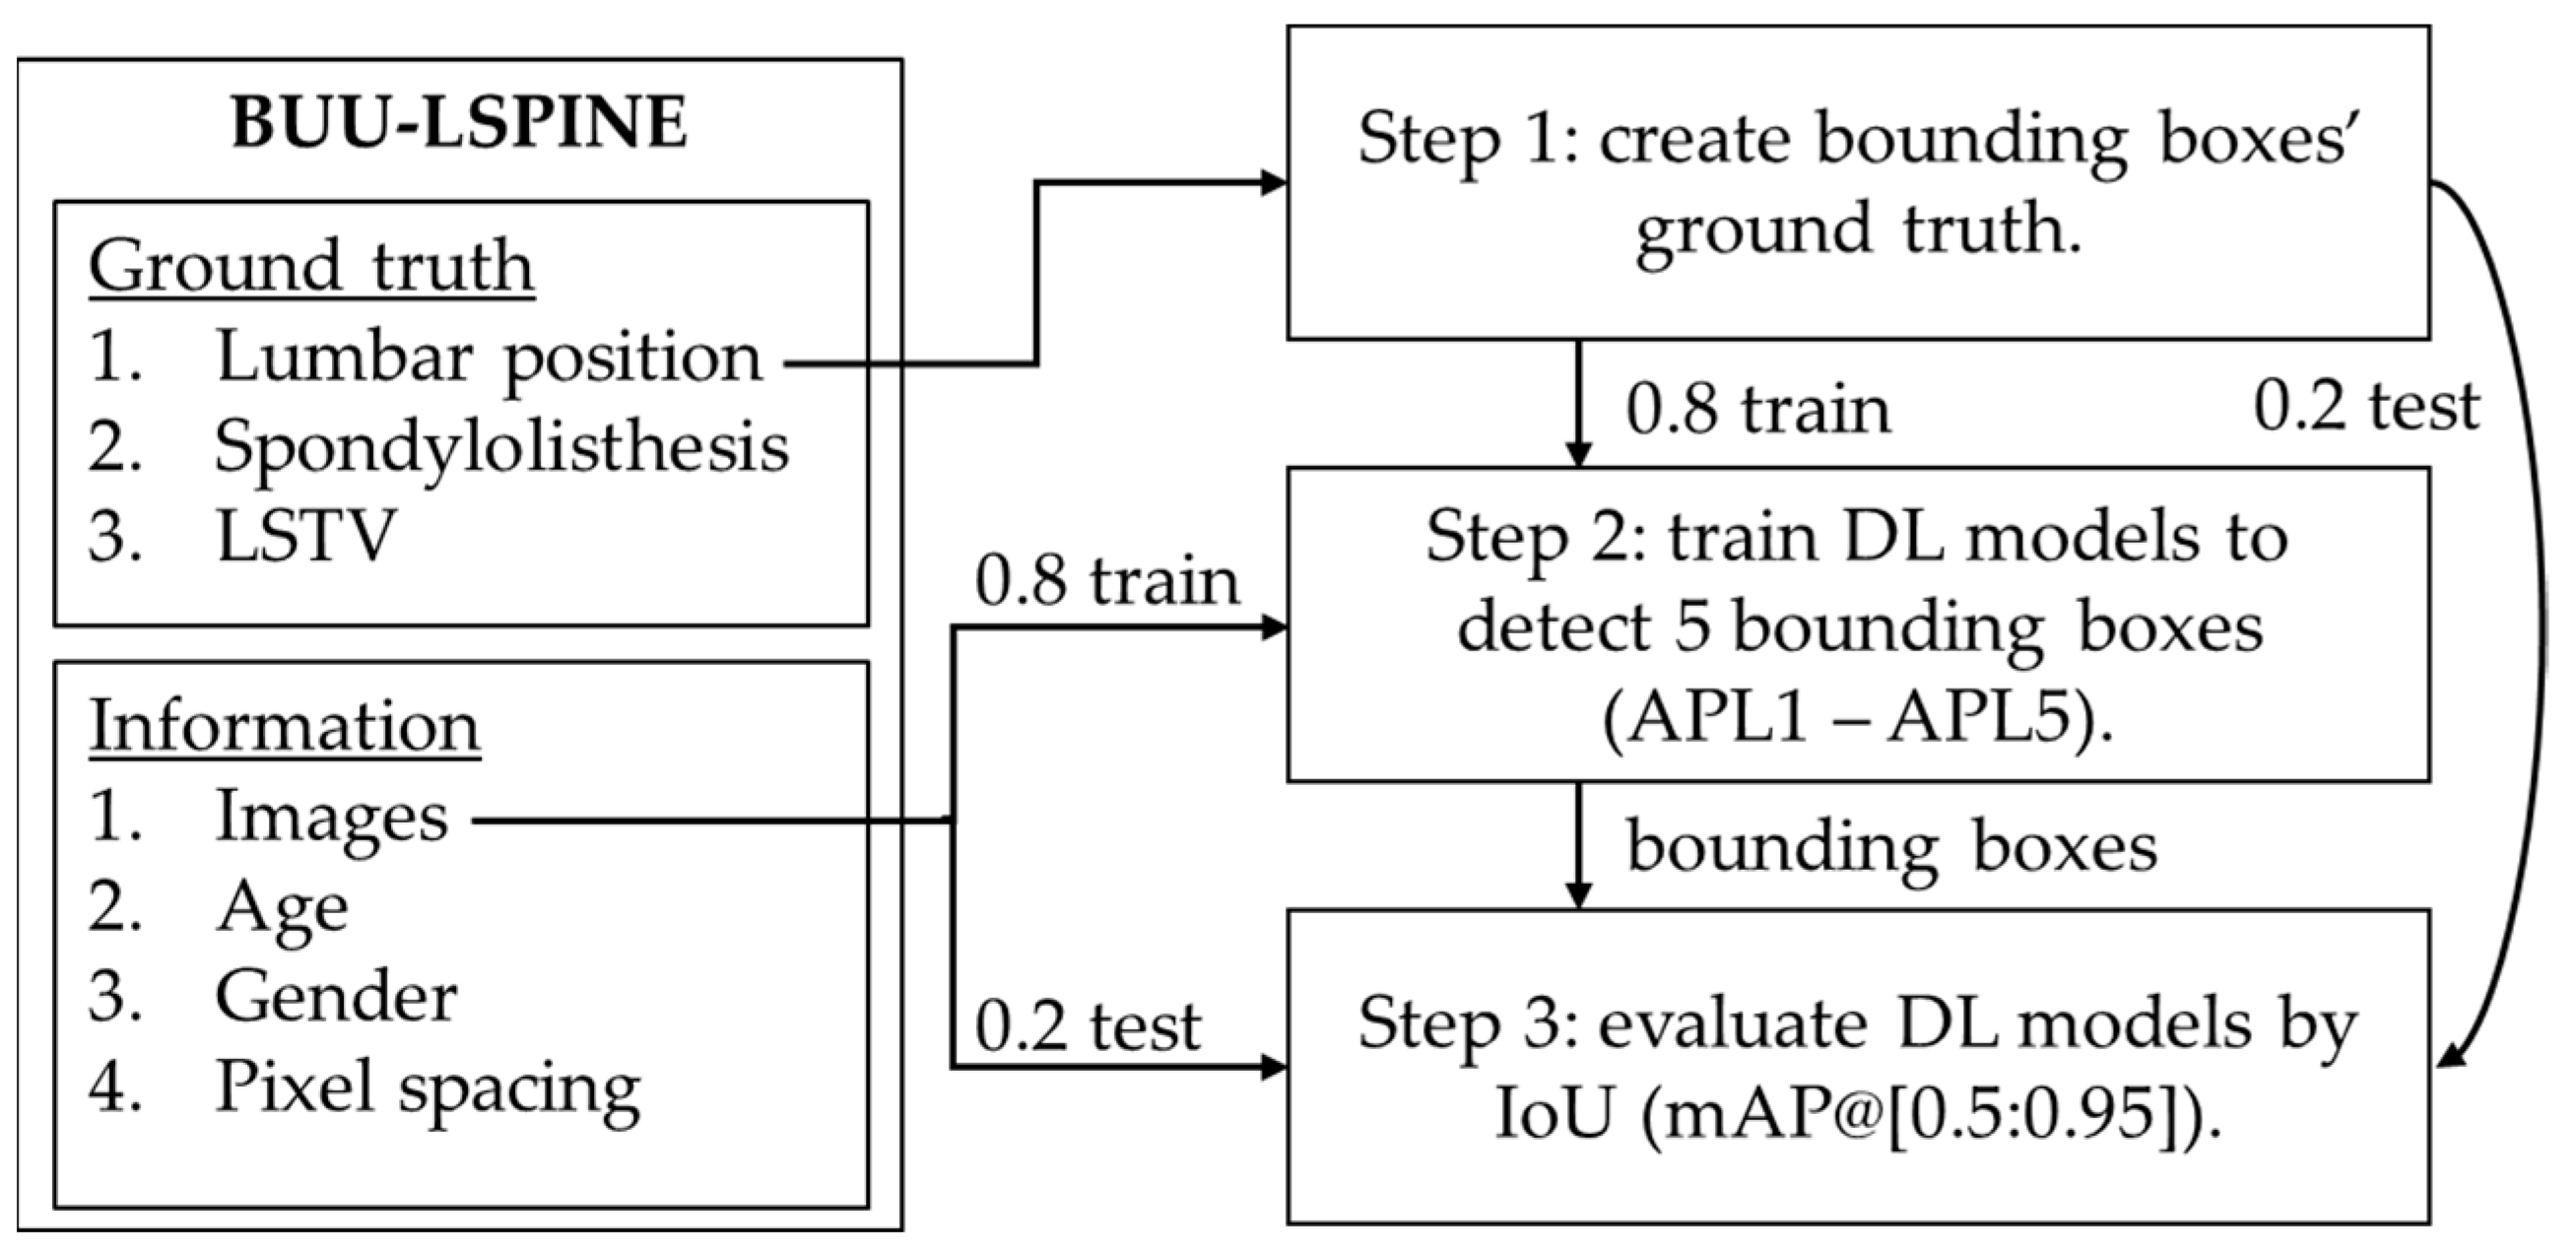

2.4.1. Lumbar Vertebrae Detection

3.1. Lumbar Vertebrae Detection